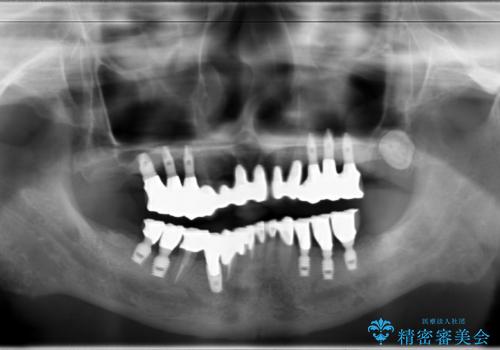

虫歯だらけ、歯周病 崩壊した口腔の再建 フルマウスリコンストラクション

費用・時間は多大にかかりましたが、今後しっかりと咬んで生活することができるでしょう。

かみ合わせの力が非常に強く、夜間の歯ぎしり・食いしばりもひどかったため、奥歯はメタルオクルーザルの設計でかぶせ物を製作しています。

インプラントの種類:Bicon / Zimmer spline

かぶせ物の種類:PFZ / PFM metal occlusal